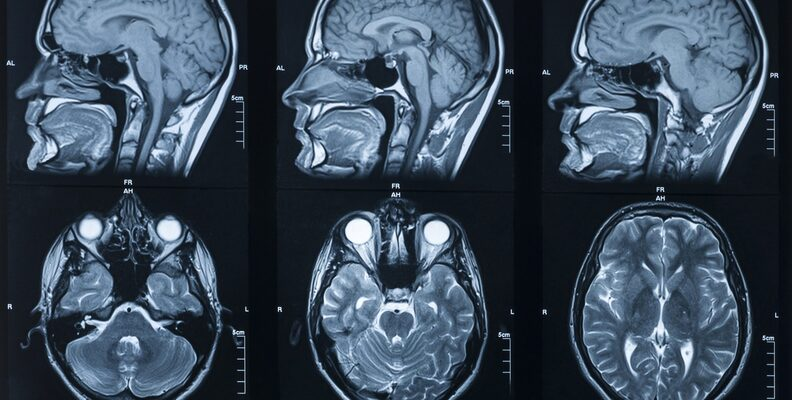

3. Brain tumor dataset 脑肿瘤医学数据集

该数据集为使用各种模型对脑肿瘤进行分类和分割的数据集,共包含 7,153 个图像,其中有 1,621 个神经胶质瘤图像,1,775 个脑膜瘤图像,1,757 个垂体图像,2,000 个无肿瘤(大脑健康)图像。

直接使用:https://go.hyper.ai/zgX7A

数据集示例